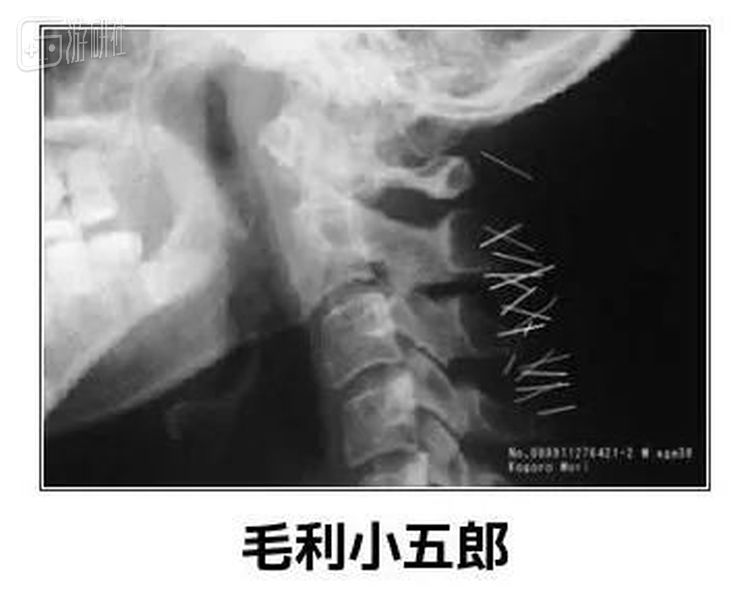

但是相比剂量,松本医生提出了一个更值得注意的危险点,“就算麻不死,小五郎脖子后面插着的50根麻醉针可是也够要命的了”。

“如果这些随着血管流到肝动脉、流到心脏或者头部就完蛋了”,松本医生解释道,“眠之小五郎将达成永眠”。